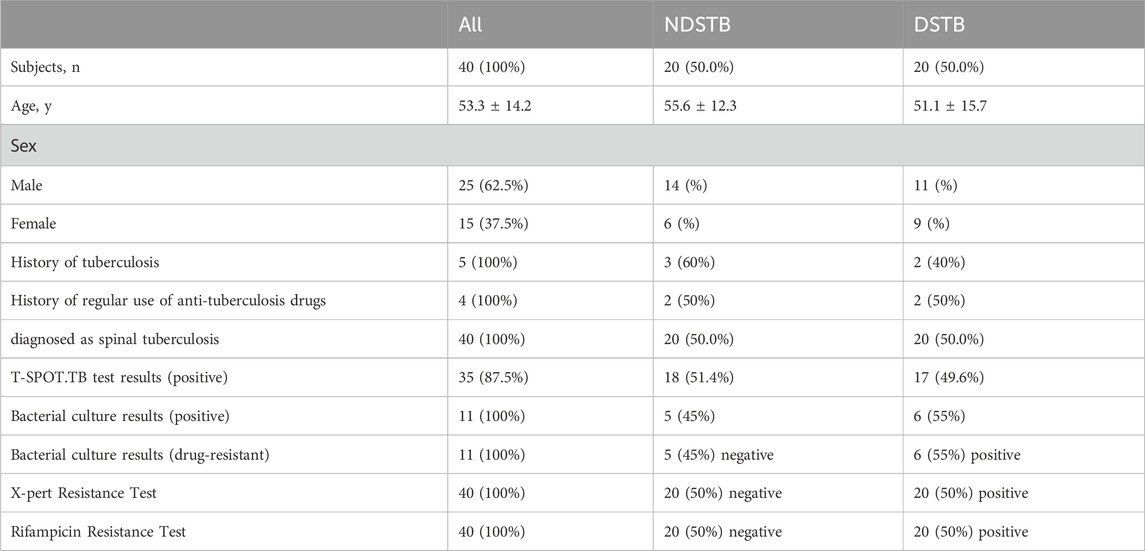

ResultsParticipant baseline characteristicsIn the NDSTB group, there were a total of 20 participants, including 6 females and 14 males, with an average age of 55.6 ± 12.3 years. The DSTB group consisted of 9 females and 11 males, with a mean age of 51.1 ± 15.7 years (Table 2). The results showed no significant difference in age and sex between the two groups (p = 0.117, p = 0.408). All participants underwent questioning and testing for radiographic manifestations, T-SPOT.TB, Bacterial culture, X-pert Resistance Test, and Rifampicin Resistance Test in hospitals, with statistics recorded accordingly to the actual situation. Additionally, radiographic manifestations of spinal tuberculosis were documented and compared with those of a normal spine (Figure 2).

Figure 2. Radiographic manifestations of spinal tuberculosis. (A) Radiographic manifestations of spinal tuberculosis (indicated by arrows). (B) Imaging features of a normal spine.